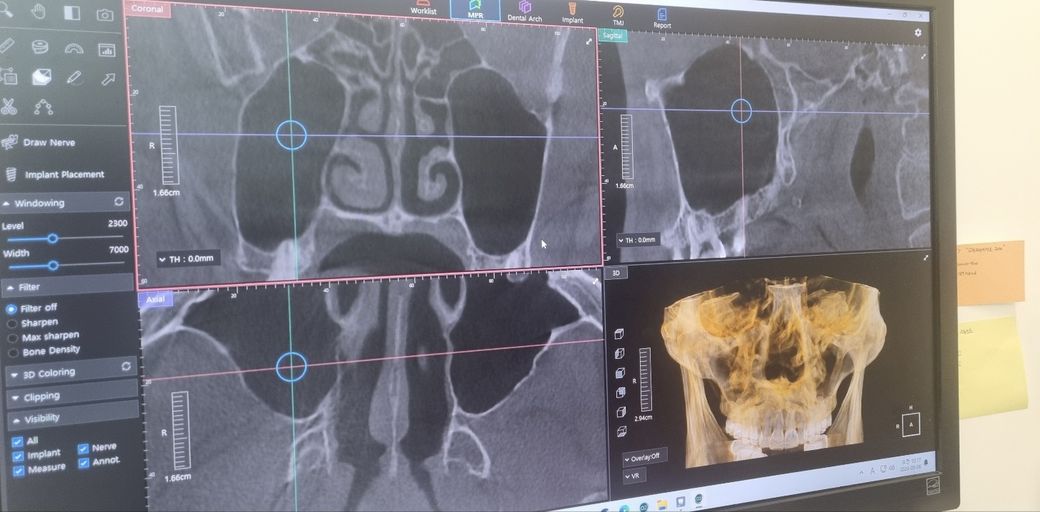

이게 치과가서 ct나 엑스레이를찍어보니까 별문제는없는데 혹시 비염있냐고 물어보시더라고요 근데 제가 콧물은잘안나고 코가 좀막힌듯한 증상이있는데 이것도 비염중에 있는 증상이라고하더군요

치과에서는 자세히는 모르는데 ct상 비염인지 부비동염인지 의심간다고 해서 일단 이빈후과가보라는데

혹시 ct사진중에 비염에 의심갈만한게 보이는지 궁금합니다 사진이 깔금하게 안나온점은 죄송합니다

• 1번 째 사진

올려주신 사진에서 부비동에 염증 소견은 저명하지 않으나 오른쪽 코 점막이 부어 있어 비염의 가능성이 생각됩니다.

불편증상이 있다면 이비인후과 진료를 바랍니다.